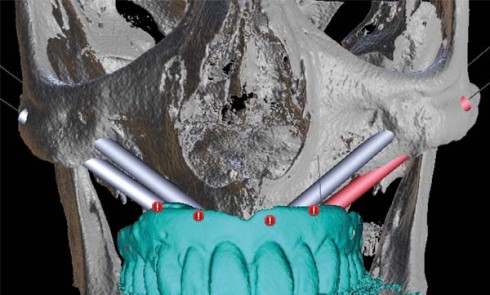

Article réservé à nos abonnés Parodontites terminales et échecs de réhabilitations implantaires maxillaires

Les indications L’état de délabrement des dents maxillaires ou du parodonte conduit parfois à poser l’indication d’une édentation totale. Une...

Article réservé à nos abonnés Réhabilitation chirurgico-implanto-prothétique immédiate :

L’exérèse chirurgicale de processus néoplasiques bénins ou malins est la principale cause des pertes de substance acquises maxillo-mandibulaires. À la...